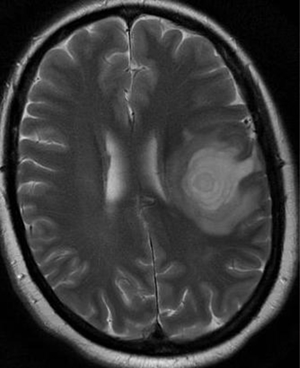

Концентрический склероз – это острая форма рассеянного склероза, которая характеризуется специфическим течением и отличается многослойным концентрическим строением демиелинизированных участков в головном мозге.

В белом веществе образуются участки разрушения миелина, которые приобретают форму колец и завитков.

По морфологическому строению демиелинезированные участки похожи на чередование зон без миелина и церебральной ткани с восстановленным или сохраненным миелином.

МРТ головного мозга позволяет определить наличие заболевания еще при жизни.